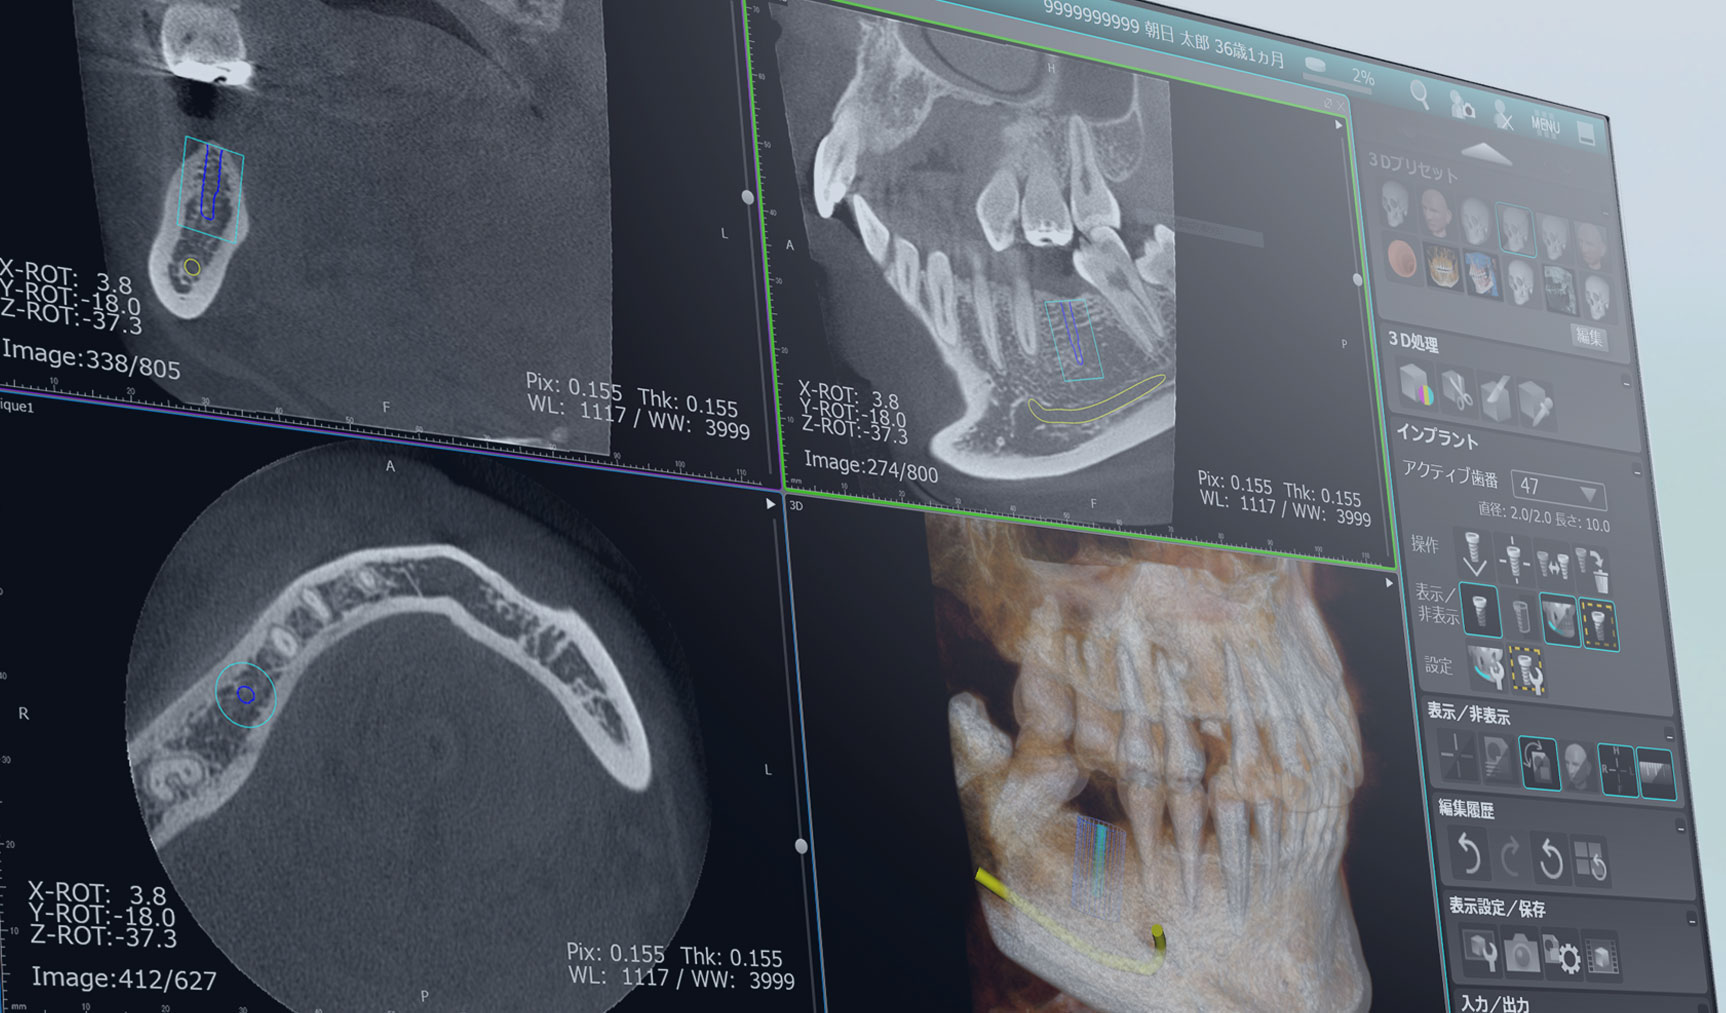

駒沢よしや矯正歯科では、より正確で安全な診断を行うために歯科用CT(コンビームCT)を導入しています。この技術により、従来のエックス線写真では得られない詳細な情報を確認し、患者さま一人ひとりに治療計画を立てることが可能です。

歯科用CT(コンビームCT)は、歯や顎骨、神経、血管などを三次元(3D)で映し出すことができる画像診断装置です。

- 親知らずの抜歯や埋伏歯の診断

- 顎関節症の診断

- 骨の成長や形態の詳細な確認

- インプラント治療を検討している場合

安心・安全な検査環境で、正確な診断と効果的な治療計画を。7 歯科用CT

歯科用CTで得られる情報

顎骨や歯の詳細な構造

骨の密度や形状、歯根の位置などを正確に把握します。

歯の埋伏や異常の確認

親知らずや埋伏歯の位置を詳しく診断します。

神経や血管の位置の確認

矯正治療や外科処置において、神経や血管を傷つけないよう計画を立てます。

病変や異常の発見

顎の中に隠れた病変や異常を早期に発見することが可能です。

歯科用CTのメリット

診断の精度向上

平面のエックス線写真では見えなかった部分も3D画像で確認できるため、診断の精度が格段に向上します。

治療の安全性を確保

歯や顎骨の状態を立体的に把握することで、安全かつ効果的な治療が可能です。

患者さまへのわかりやすい説明

3D画像を使って治療計画を説明するため、患者さまも自身の状態をより理解しやすくなります。

駒沢よしや矯正歯科の歯科用CT

当院では、歯科用CT機器を使用して、放射線量を最小限に抑えた安全な撮影を心がけています。短時間で撮影が完了するため、患者さまの負担も軽減されます。

歯科用CTが必要なケース

安心して治療を受けられるために

駒沢よしや矯正歯科では、歯科用CTを活用して精密な診断と治療計画を提供しています。

セファログラム(頭部エックス線規格写真)・歯科用コンビームCT

矯正治療では、歯並びだけでなく、あごの骨格や歯の位置を丁寧に確認することが大切です。必要に応じてセファログラムや歯科用コンビームCTを用い、診断と治療計画に役立てています。